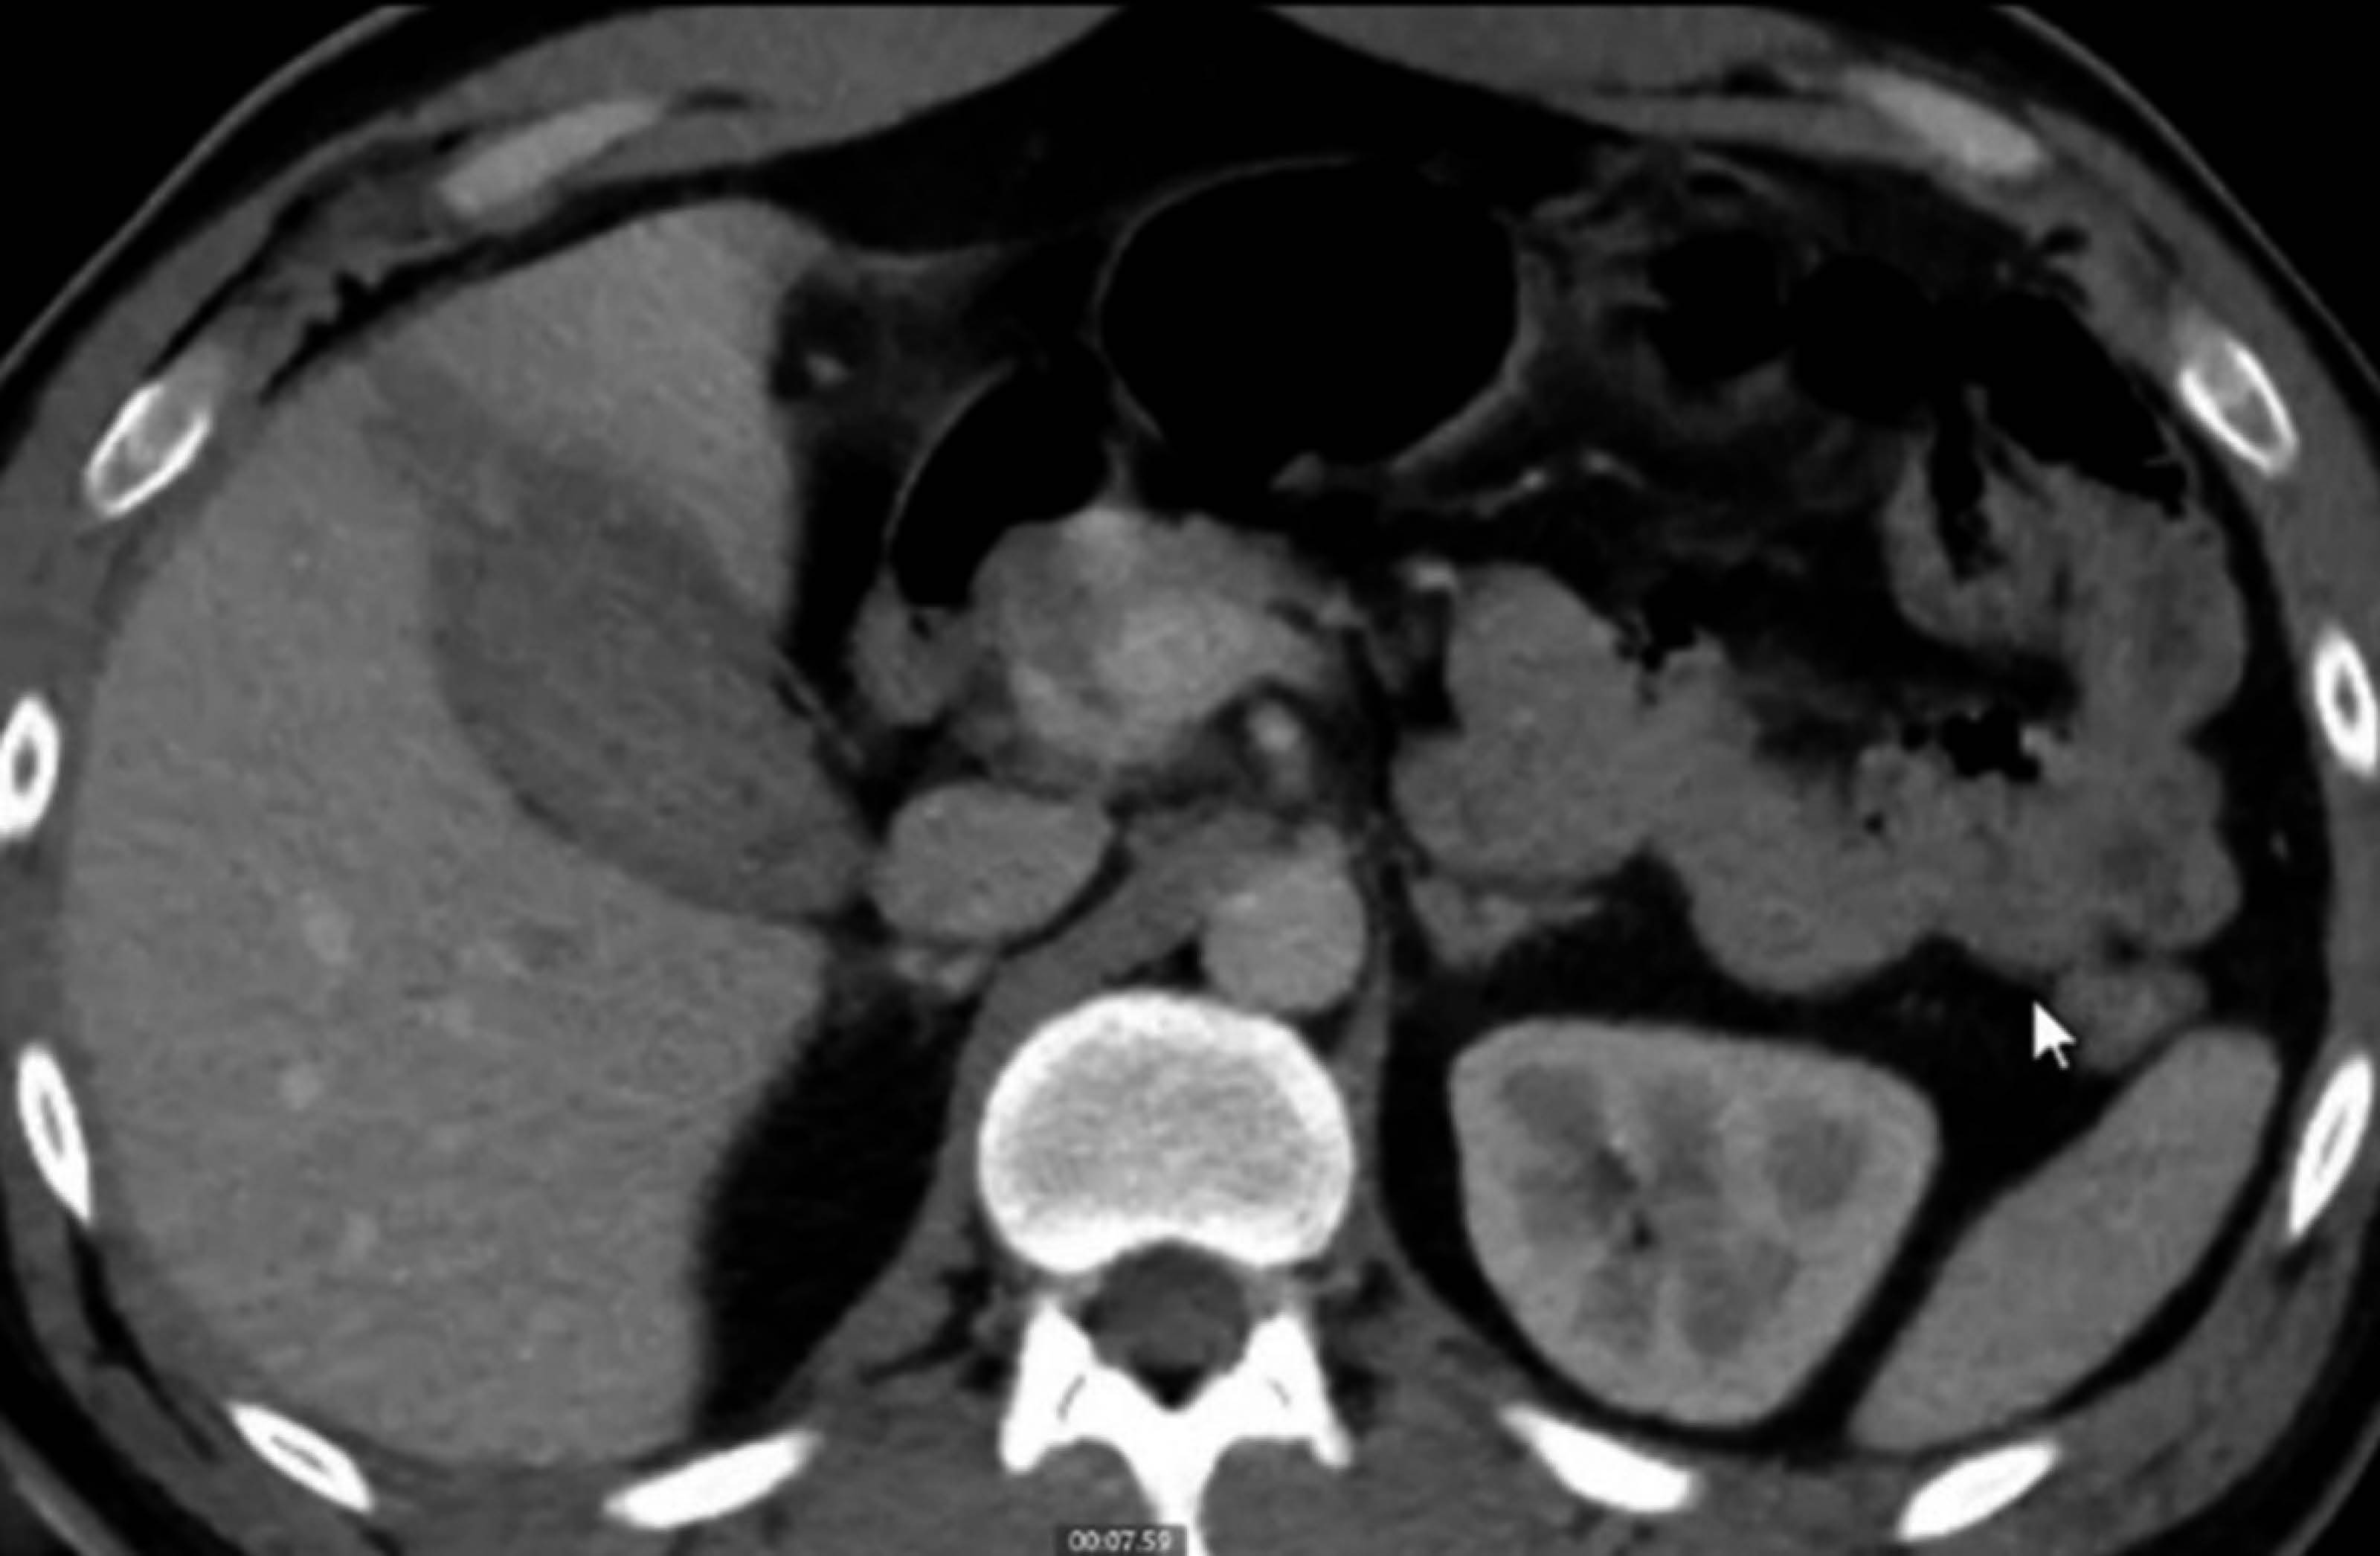

The patient continued without signs of peritoneal irritation or acute abdomen, although due to probable hemobilia, a computed tomography (CT) scan of the abdomen was requested 29 hours later that showed a hepatic laceration of segment V grade I of the AAST and a gallbladder measuring 81 × 44 × 48 mm with heterogeneous content, as described in Figure 3.

A pathognomonic sign of perforation is the extravasation of intraluminal contrast through the lesion associated with perihepatic fluid.1 Therefore, since the patient was stable with no evidence of shock that did not warrant an urgent surgical management, an abdominal CT scan was requested, reporting probable hematic content in the gallbladder, with no evidence of a continuity solution in the gallbladder wall.